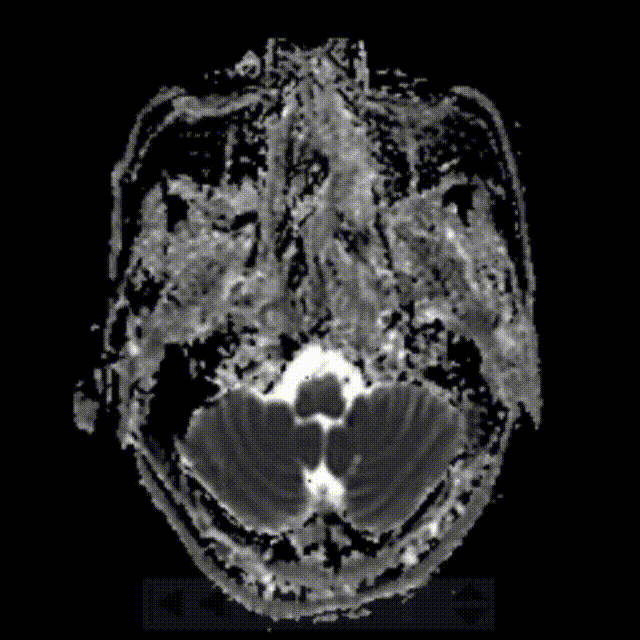

术后第二天影像。